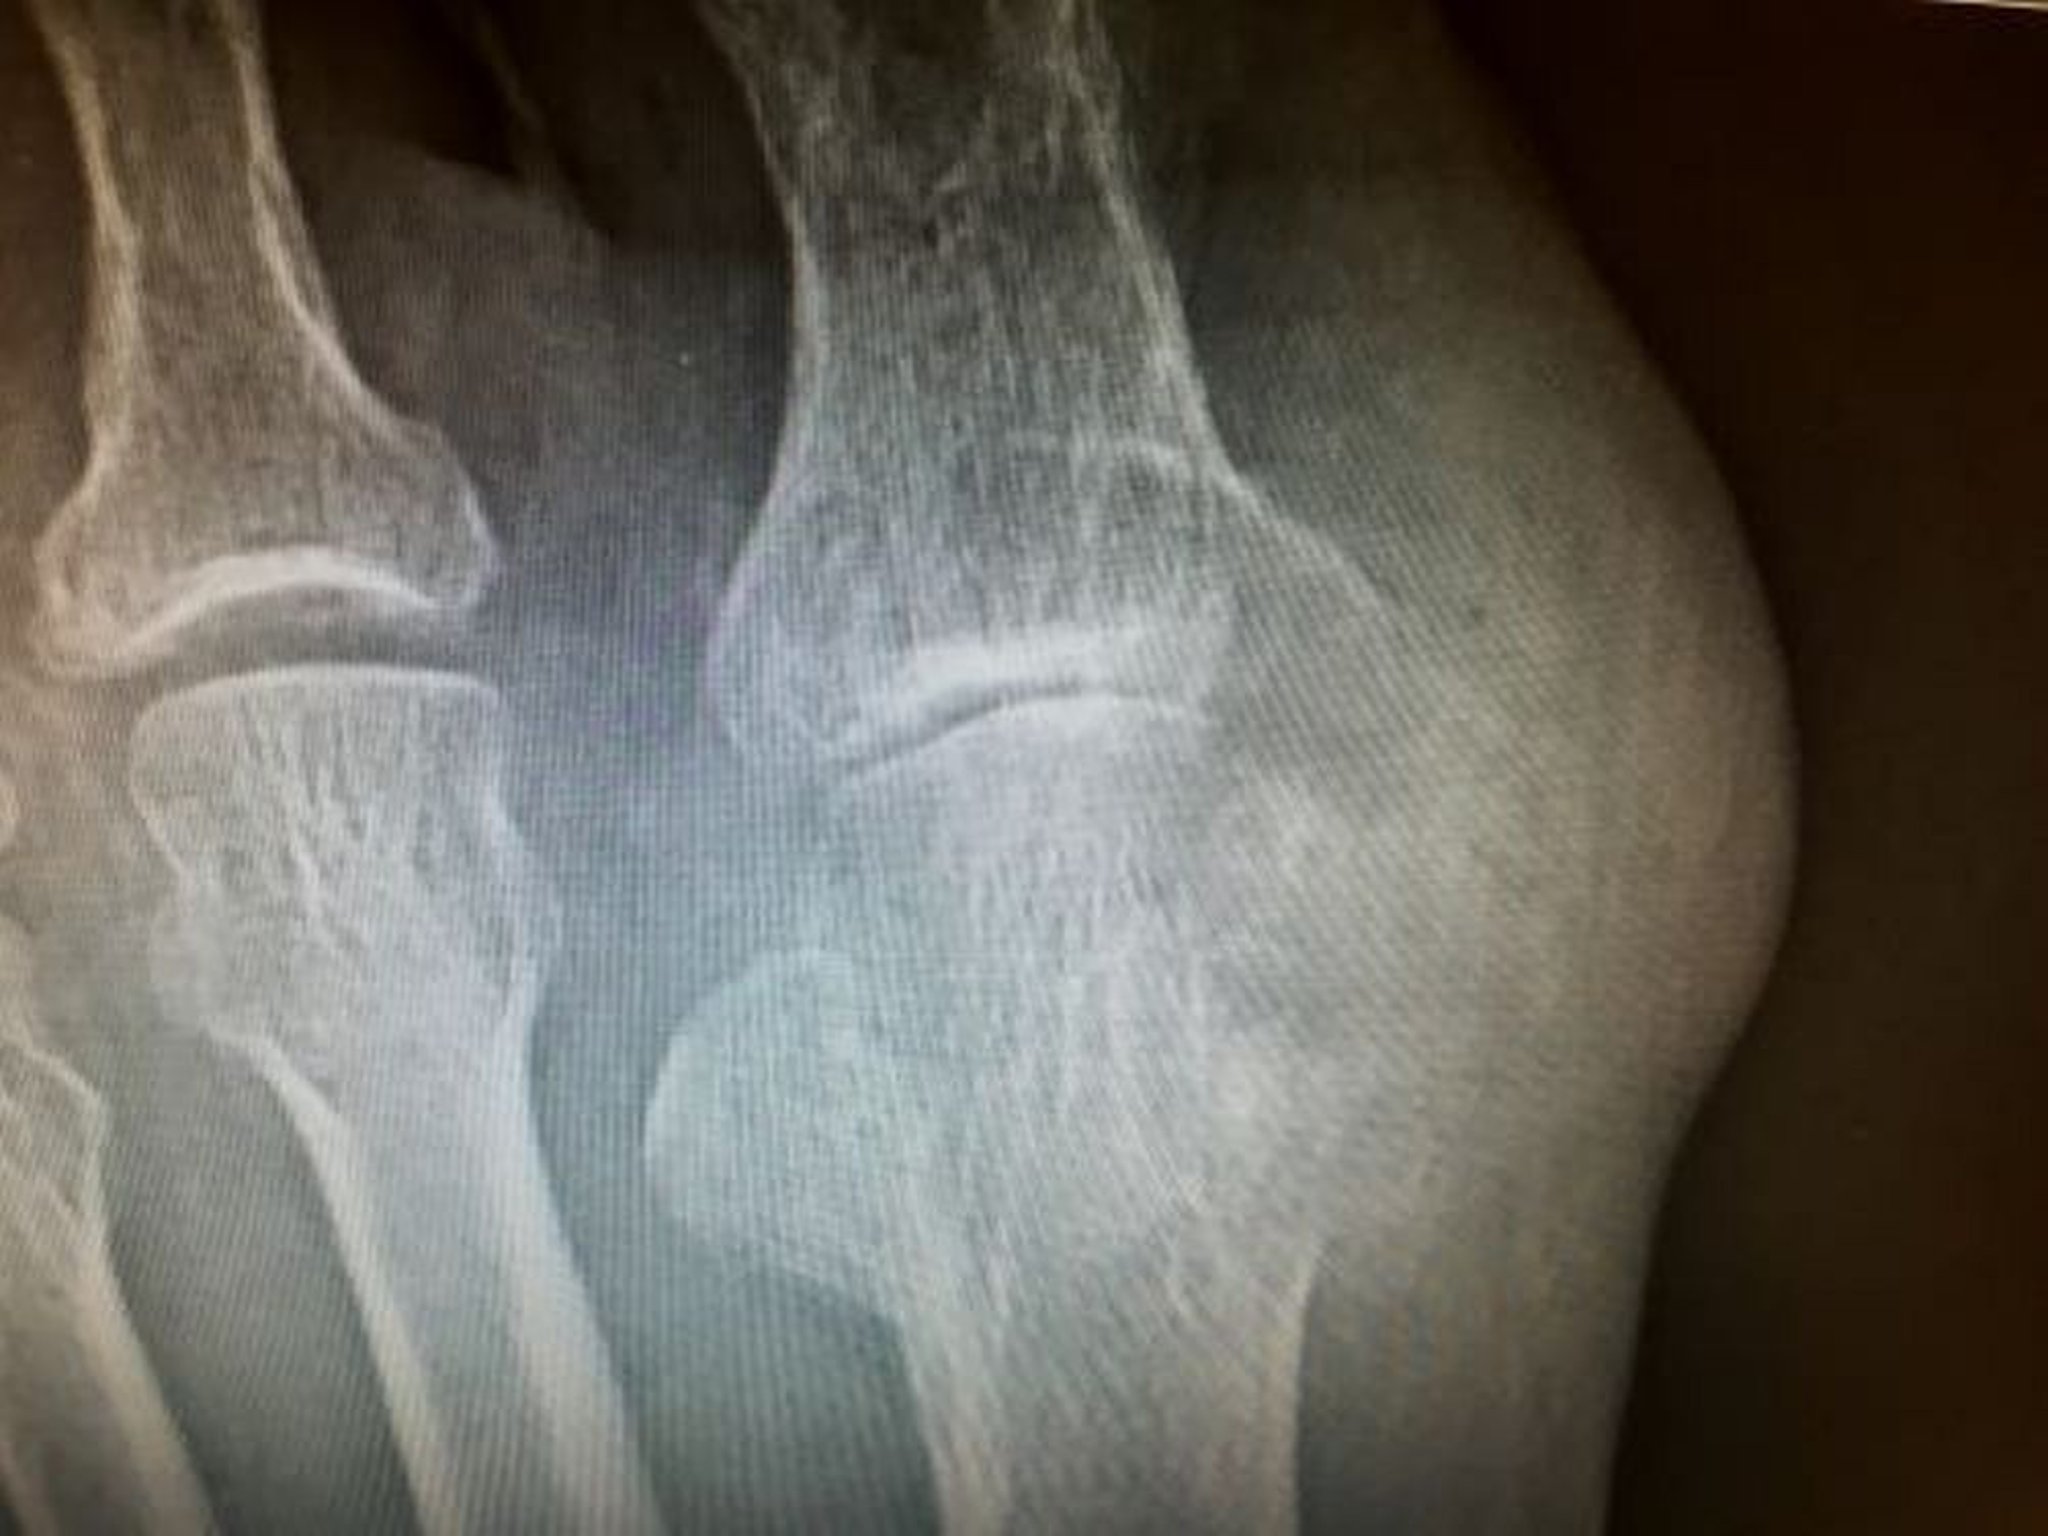

骨びらんまたは痛風結節を検索するために罹患関節のX線撮影を行ってもよいが,関節液検査で急性痛風の診断が確定している場合は不要であり,初回発作時にびらんが認められることはまれである。ピロリン酸カルシウム関節炎では,ときに放射線不透過性の沈着物が線維軟骨,関節の硝子軟骨(特に膝関節),またはその両方にみられることがあるが,石灰化は急性発作がなくとも認められる可能性がある。

慢性痛風性関節炎の診断

原因不明の関節疾患が遷延しているか,皮下または骨に痛風結節がみられる患者では,慢性痛風性関節炎を疑うべきである。第1中足趾節関節または他の罹患関節の単純X線が有用となることがある。それらのX線では,張り出した骨縁辺とともに軟骨下骨の打ち抜き病変を示すことがある(第1中足趾節関節で最もよくみられる);病変がX線で目に見えるようになるには直径が5mm以上でなければならない。関節裂隙は,典型的には疾患経過のかなり後期まで保たれる。通常は,罹患関節の慢性貯留液から得られる滑液所見で診断に至る。